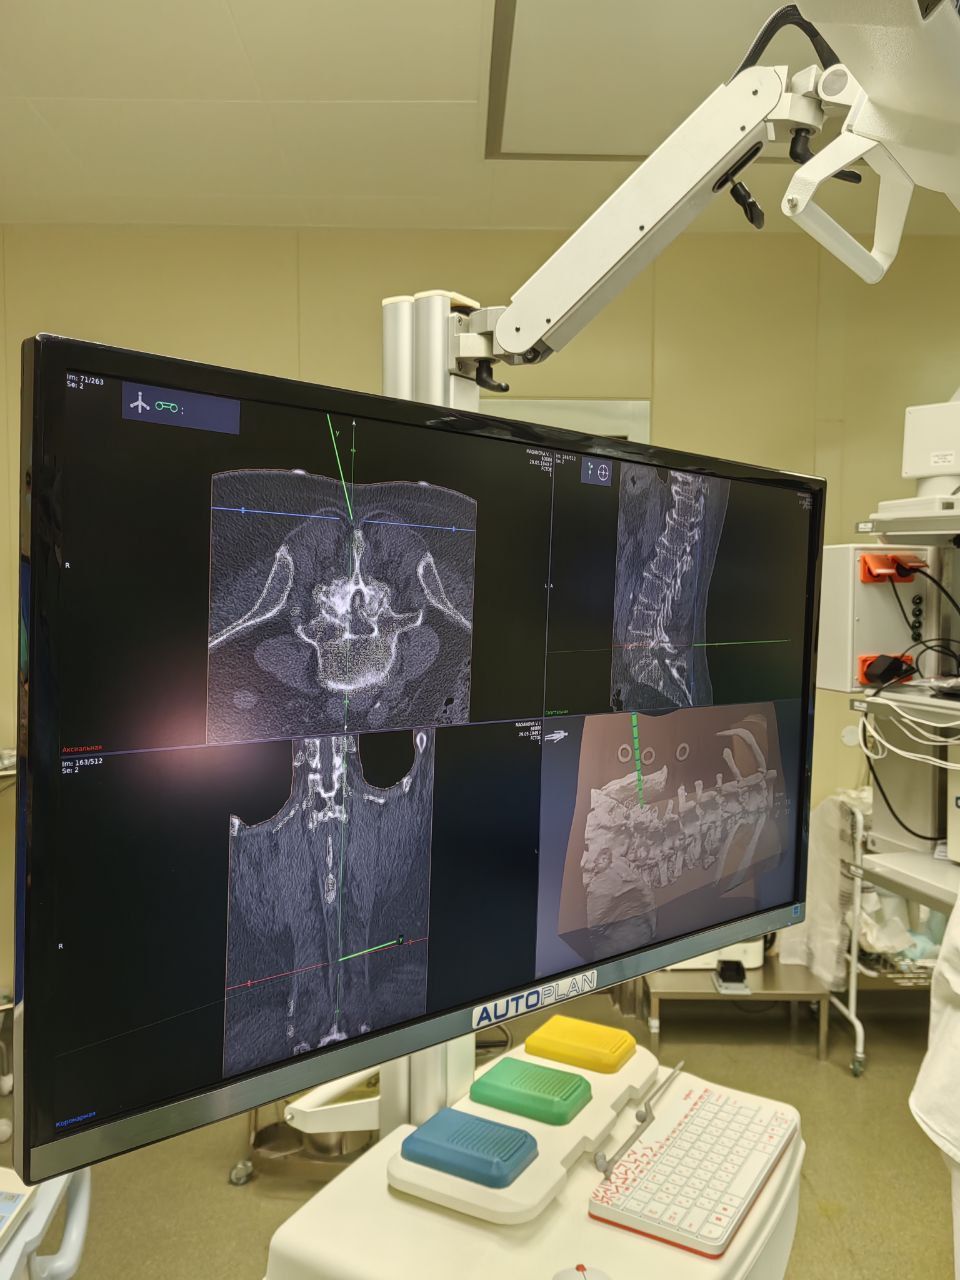

Заведующий отделением травматологии и ортопедии №4 ФГБУ «ФЦТОЭ» Минздрава России (г.Барнаул), врач-травматолог-ортопед, врач-нейрохирург высшей квалификационной категории, кандидат медицинских наук Андрей Игоревич Васильев принял участие в апробации системы хирургической навигации AUTOPLAN

Это инновационная разработка ученых Самарского государственного медицинского университета, которая помогает хирургам эффективно планировать и с особой точностью выполнять операции.

«В рамках сотрудничества с СамГМУ и его технологическим кластером мы апробировали отечественную систему интраоперационной нейронавигации AUTOPLAN, провели первое хирургическое вмешательство. Данный вид работы оставил положительные впечатления: система хирургической навигации позволяет непрерывно отслеживать хирургические инструменты относительно анатомических структур пациента, избегая повреждения функционально значимых зон. Отрадно видеть качественное отечественное оборудование, которое может конкурировать с заграничным», — отметил в разговоре о результатах работы Андрей Игоревич Васильев.